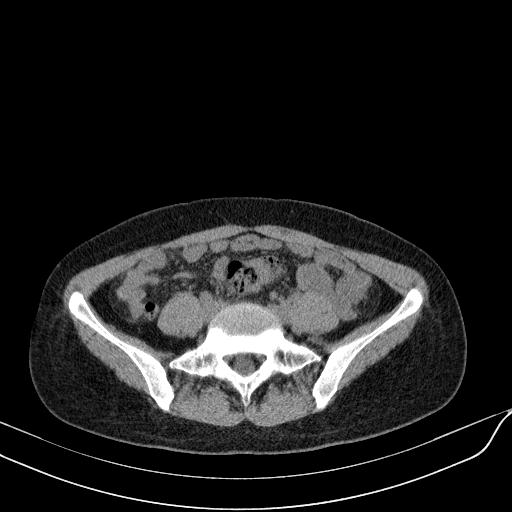

标题: CT23965:无外伤史,下腹痛 [打印本页]

标题: CT23965:无外伤史,下腹痛

肠道未准备,继续往下扫,乙状结肠占位不排除。建议钡灌或结肠镜检查。

乙状结肠占位不排除

未见明显异常改变,做个气钡双重造影除外一下结肠病变,无外伤史为啥不常规喝泛影葡胺水对比剂再扫ct呢?

扫描时应做肠道准备,口服稀释造影剂。

肠道肿瘤,建议行钡剂灌肠检查。